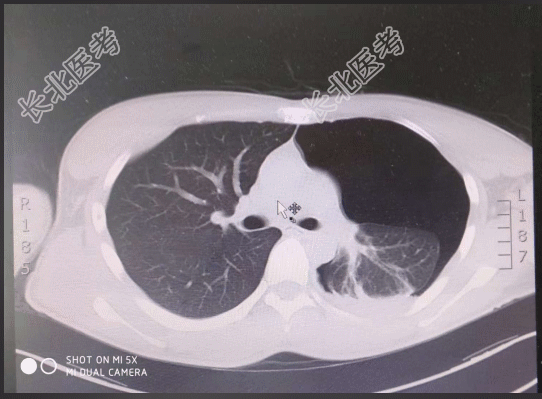

- [材料题] 【一般资料】男性,19岁,学生【主诉】剧烈运动后出现左侧胸痛,伴胸闷1天【现病史】患者1天前,跳远后后出现胸痛,呼吸时明显,休息后无缓解,伴有胸闷,无咳嗽、咳痰,无发热,无放射性疼痛,无咯血、晕厥,2018-10-20门诊行肺CT检查阅片提示:左侧气胸,为求进一步诊治,门诊拟“气胸”收入我科,病程中患者神清,精神可,饮食一般,睡眠一般,大小便正常,体重未测。【既往史】一般健康状况良好;否认高血压病史。否认糖尿病病史。否认冠心病病史。否认慢性支气管炎病史。否认胆结石病史。否认胆囊炎病史。否认“肝炎、伤寒”等传染病病史。未发现药物、食物过敏史。无手术史。否认输血史。【查体】T:36.3℃,P:75次/分,R:20次/分,BP:118/75/mmHg。神清,精神可,步入病房,自动体位,言语清晰,查体合作。皮肤黏膜:无黄染皮疹,无瘀点、瘀斑,无紫绀水肿。浅表淋巴结未触及肿大。头部无畸形,双瞳孔等大等圆3mm,对光反射存在;外耳道无脓性分泌物,听力正常;鼻畅,鼻腔无脓性分泌物;咽无充血,扁桃体不大,伸舌居中。颈软,气管居中,甲状腺不大,颈静脉无怒张,肝颈反流征(-)。左侧胸廓呼吸运动减弱,触觉语颤减弱,叩诊呈鼓音,听诊左侧呼吸音减低,未闻及明显干湿啰音;心率76次/分,律齐,各瓣膜听诊区未闻及明显病理性杂音。腹平软,肝脾肋下未及,无压痛反跳痛,移动性浊音(-),肠鸣音正常。脊柱四肢生理弯曲存在,活动自如,双下肢无水肿。肛门外生殖器:未检。生理反射存在,病理反射未引出。【辅助检查】胸部CT提示:左侧气胸。